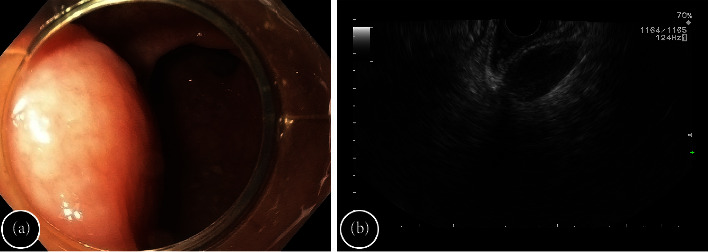

尾肠囊肿或直肠后囊肿是一种罕见的先天性病变,被认为来自胚胎后肠的一部分,通常为良性,无特异性症状或症状不明显,主要在中年女性中确诊。为避免并发症并确诊,建议对囊肿进行彻底手术切除。在本报告中,我们介绍了成功通过内窥镜治疗尾肠囊肿的经验,概述了内窥镜切除技术,并讨论了这种方法适用于哪些情况。

Tailgut cyst or retrorectal cystic hamartoma is a rare congenital lesion, thought to arise from a portion of the embryological hindgut, usually benign, with no or unspecific symptoms, mainly diagnosed in middle-aged women. Complete surgical resection of the cyst is recommended to avoid complications and confirm the diagnosis. In this report, we present our experience in the successful endoscopic management of a tailgut cyst, outlining the endoscopic resection technique and discussing under what conditions this approach may be applicable.